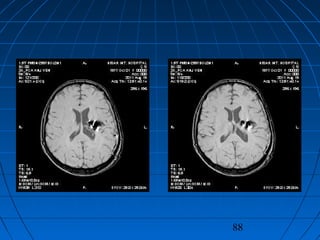

 S.Ç.: 32 yaşında kadın hastaS.Ç.: 32 yaşında kadın hasta

 Ani şiddetli başağrısı, B-KAni şiddetli başağrısı, B-K

CERRAHİCERRAHİ

 Sol frontoparyetal geniş kranyotomiSol frontoparyetal geniş kranyotomi

 AVM’nin total rezeksiyonuAVM’nin total rezeksiyonu

87

88